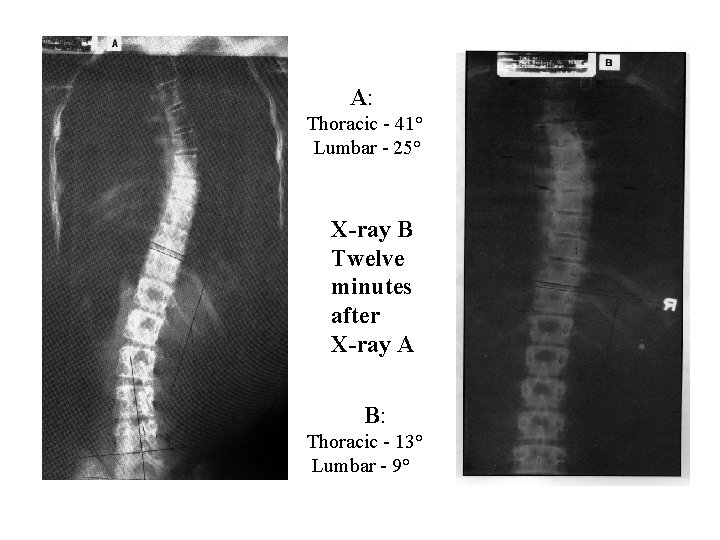

A: Thoracic - 41° Lumbar - 25° X-ray B Twelve minutes after X-ray A B: Thoracic - 13° Lumbar - 9°